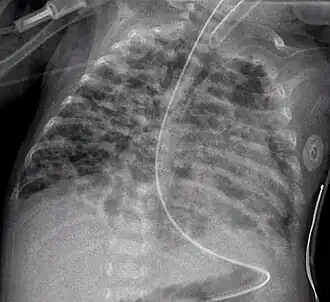

| Radiografia de displasia broncopulmonar | |

Displasia broncopulmonar é uma doença pulmonar crónica em recém-nascidos e crianças. É mais comum em crianças com baixo peso à nascença e nas que se submetem a tratamentos prolongados com ventilação mecânica para a síndrome da angústia respiratória do recém-nascido. A doença causa morbilidade e mortalidade significativas. Foi descrita pela primeira vez em 1967.[1]